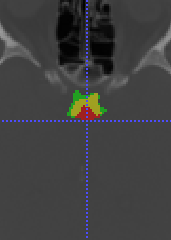

To model , we propose using a half-Gaussian distribution based on nodule size distribution because is correct if it is within the nodule area (center slice of as , and nodule size can be empirically estimated based on existing data) for nodule detection in Fig. 17(a). For lung lobe prediction , a logistic regression model is used based on relative value of nodule center after lung segmentation. That is

| (22) |

where is the associated weights with lobe location for logistic regression, feature , and is the total size of image after lung segmentation. In the experiments, we found the logistic regression converges quickly and is stable.